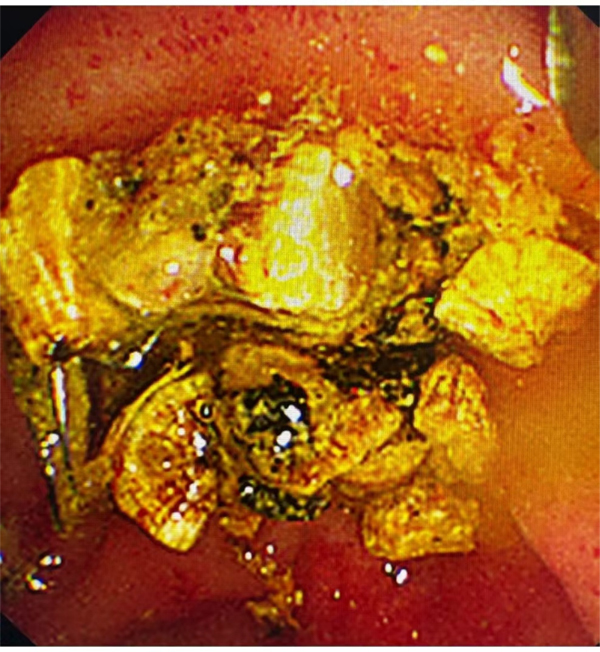

患者胆囊内充满了巨大结石

手术取出的患者胆囊结石碎块